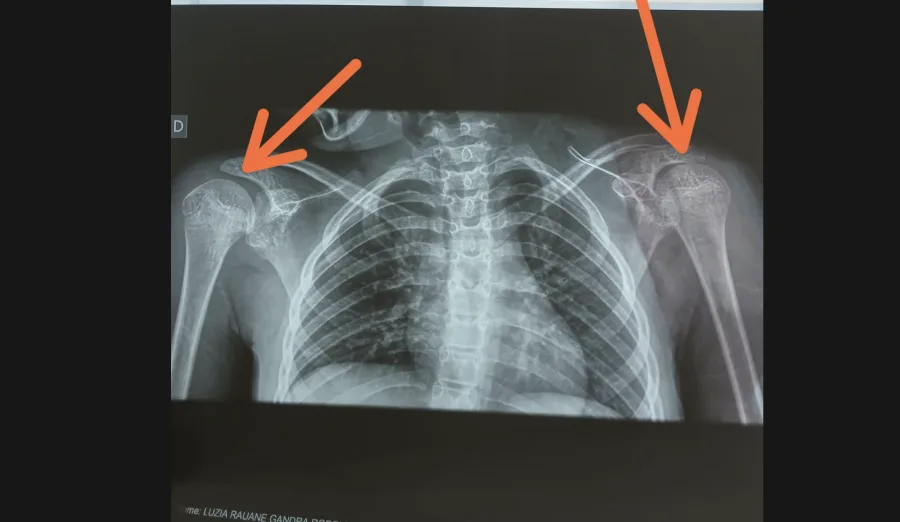

- Radiografia dos ombros e foto clínica compõem o dossiê; publicação preserva a identidade da criança.

A família acrescentou uma radiografia dos ombros realizada no mesmo período, destacando as articulações. A redação não emite diagnóstico a partir de imagem; o RX é apresentado como elemento clínico posterior ao transporte, compondo a linha do tempo dos sintomas e atendimentos.